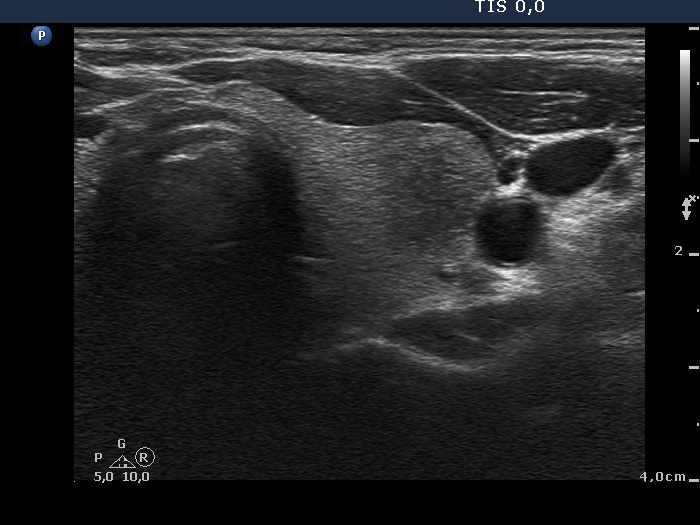

Follow-up 2 months after the first visit (3rd row of images):

Clinical presentation: Within 24 hours of the administration of 32 mg methylprednisolone, the neck complaints and subfebrility had stopped. When the patient reduced the dose to 8 mg daily for 2 weeks as suggested, the left lobe became sensitive. This tenderness has now been significantly reduced, but still persisted at times.

Palpation: The left lobe was tender on palpation.

Laboratory tests: TSH 1.62 mIU/L, FT4 9.97 pM/L, CRP 0.1 mg/L.

Ultrasonography: The right lobe decreased in size as did the extent of hypoechogenic areas in this lobe. The left lobe remained unchanged.

Suggestion: Discontinuation of steroid therapy. TSH in three months.